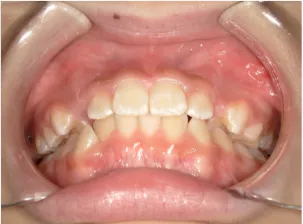

治療前①小5:生え変わり後期のため顔の成長を促進させる目的で拡大装置(アーチ形態の修正)と上顎前歯をそろえることを先行し、できるだけ非抜歯治療で進める予定を提案しました

| カウンセリング・診断結果 | 治療方法は精密検査、分析をして検討することをご理解いただき、矯正治療で抜歯をするかしないかの違いについて説明し治療を希望されたので精密検査を行いました。 精検の結果、顔立ちは下顎が後退したタイプの出っ歯(下顎後退型上顎前突)でV-shaped arch(歯列が狭い)、凸凹、八重歯になっていて、機能的にはべろのポジションが悪い低位舌があります。 口元は問題ありません。 |

| 行ったご提案・診断内容 | 生え変わりが終わってなくマルチブラケット法による咬合治療には早い時期のため、顔立ちの成長を促す目的で歯列弓(アーチ)の拡大と前歯を並べながら永久歯が生えるのを待ち、咬合治療開始時に再診断で抜歯、非抜歯を最終検討する提案をしました。 再診断時(写真②)、歯列の拡大と上顎前歯の並べ替えはされていましたが八重歯となったため抜歯、非抜歯を検討しました。 口元は特に問題がなく非抜歯で八重歯を改善するためのスペースを作ることが可能なため非抜歯治療を提案しました。 治療は、 ・拡大および上顎左右6を遠心移動させてスペースを作る 予定装置 |